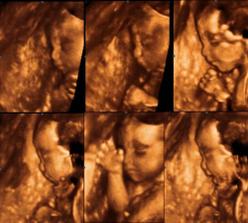

9.9.09 - 4D UTZ k výročí svatby :o) - krásný zážitek, UTZ sice trochu nestíhal naši hyperaktivní ženštinu, ale stálo to za to